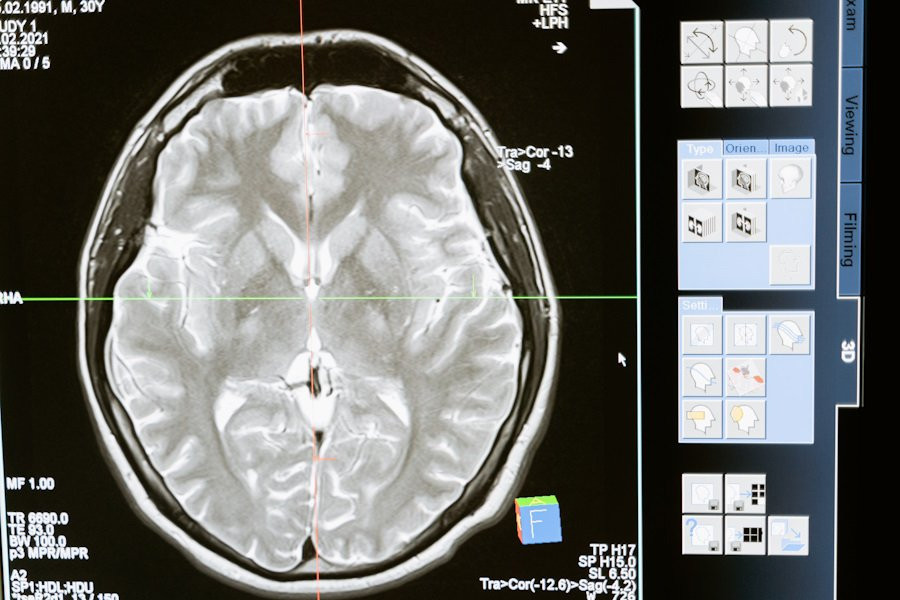

Группа ученых из Института цитологии и генетики СО РАН и ТПУ совершила прорыв в области медицинской науки, обнаружив способность наночастиц проникать в клетки нейронов обонятельных луковиц носа, сообщается на РИА Новости.

Исследователи утверждают, что эти частицы могут быть управляемы с помощью переменного магнитного поля, что открывает двери для направленной доставки в специфические участки головного мозга и воздействия на его функции.

Согласно обнародованным данным, эта методика предоставляет новые перспективы для лечения нейродегенеративных заболеваний. Предыдущие попытки управления нейронами с применением наночастиц осуществлялись извне, однако в данном исследовании удалось продемонстрировать способность даже простых нанороботов проникать внутрь нейронов, что открывает новые горизонты для медицинской науки.

Эти результаты исследования могут иметь значительное влияние на область медицины. Направленная доставка нанороботов в глубокие участки головного мозга открывает возможности для новых методов лечения нейродегенеративных заболеваний. Также данная технология может использоваться для доставки лекарственных препаратов, включая те, которые направлены на лечение опухолей головного мозга.